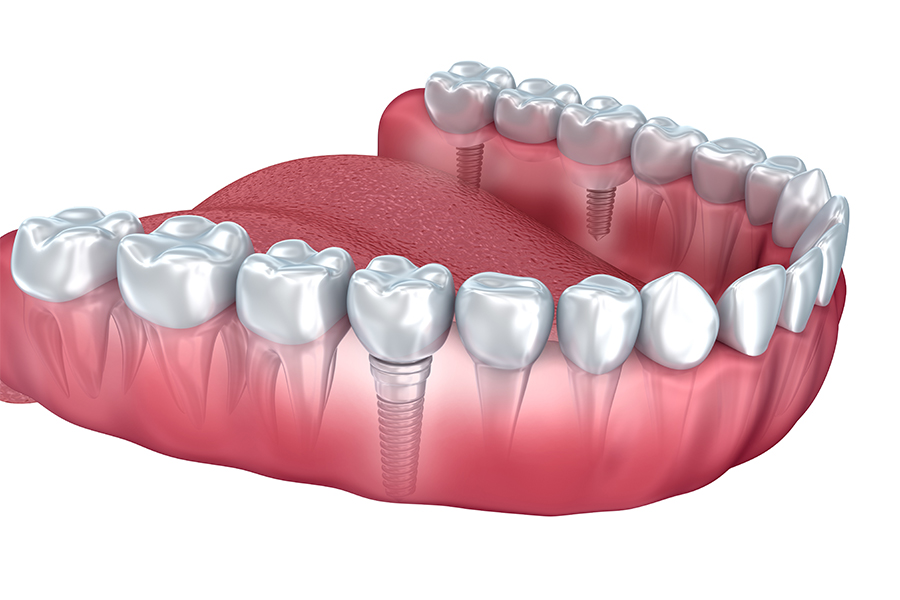

インプラント治療とは、歯が失われてしまった部分に人工の歯を埋入する治療のことです。人工の歯根を顎の骨の中に埋め込み、その上に人工の歯を固定します。

入れ歯やブリッジと異なり、隣の歯を削って負担をかけることもありませんし、自分の歯と同じような感覚で違和感なく噛むことができるようになります。また、下顎の総入れ歯が不安定で動いてしまう方や、上顎の総入れ歯で口蓋が無いものを使用される場合などには、インプラントによって入れ歯を固定する方法も有効です。

インプラントは、人工歯根を顎の骨に埋め込み、骨と結合させることで、ご自身の歯のようにしっかり噛めるようにする治療法です。